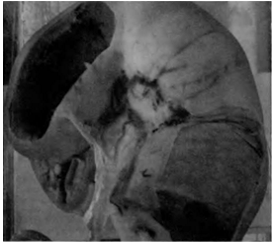

рис. 2. Мочеполовые органы самки

- ректогенитальное углубление; 2 - пузырногенитальное углубление; 3 - уретра; 4 - лоннопузырное углубление; 5 - влагалищное кольцо; 6 - тазовое сращение; 7 - влагалищный вырост брюшины; 8 - жировое тело; 9 - брыжейка матки (мезометрий); 10 - влагалищный вырост брюшины; 11 - круглая связка матки; 12 - параметрий; l3 - периметрий; .14 - матка; 15 - маточная артерия и вена; l6 - внутренний подниматель; 17 - круглая связка матки; 18 - брыжейка матки (мезометрцй); 19 - круглая связка матки; 20 - собственная связка яичника; 21 - брыжейка яичника; 22 - поддерживающая связка яичника; 23 - яйцевод; 24 - рог матки; 25 - поперечное положение двенадцатиперстной кишки; 26 - восходящее положение двенадцатиперстной кишки; 27 - проксимальная брыжейка яичника; 28 - яичниковая артерия и вена; 29 - дистальная брыжейка яичника; З0 - брыжейка яйцевода; 3l - яичник; 32 - яичниковая бурса; 33 - яйцевод; 34 - отверстие яичниковой бурсы; 35 - сосок.